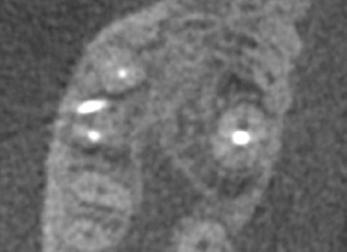

on the crest of the ridge in the region of teeth Nos. 15-25. While creating the incision, bleeding was noticed in the region of tooth No. 15 which intensified during the flap reflection (Figure 2). Bleeding was pulsatile, indicating an arterial bleed. Initially attempts to control bleeding included a pressure pack and ice pack, and the bleeder was isolated, and the vessel ligated (Figure 3). The bleeding could be controlled, and the procedure was completed by placing four Bioner implants (Bioner, Spain), size 4/10 mm. Sutures were placed, and patient was kept on basic medication for pain and infection control. Immediately after the surgery, the patient was advised to get a CBCT. As shown in Figure 4, a coronal view and Figure 4B (yellow arrows), the position of the artery can be seen.

Figure 1: Pre-op panoramic radiograph Figure 2 (left): Alveolar antral artery (AAA). Figure 3 (center): The artery has been ligated with suture. Figures 4A and 4B (right): CBCT post-implant placement and position of the artery coronally (top). 4B. Showing the position of alveolar antral artery (AAA) in relation to implant placement as indicated by the yellow arrows (bottom)